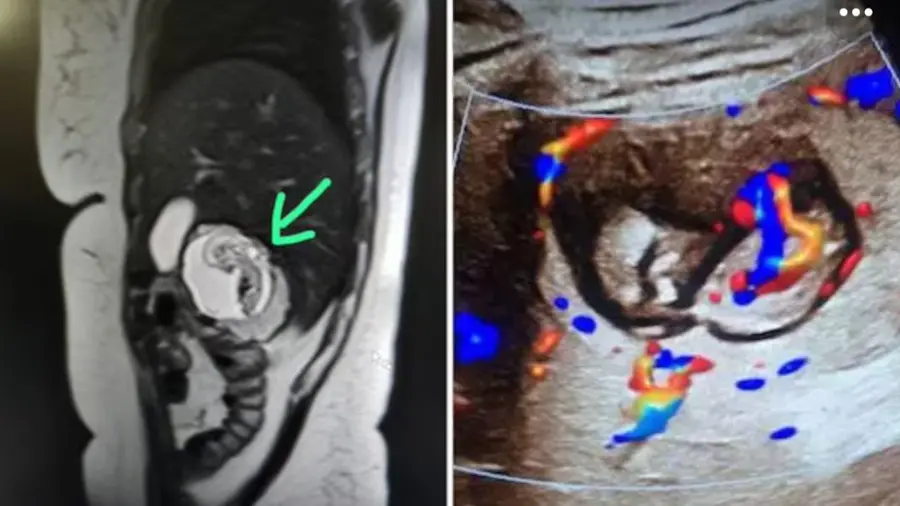

ലഖ്നൗ: ഉത്തർപ്രദേശിലെ ഒരു സ്ത്രീയുടെ കരളിൽ ഭ്രൂണം വളരുന്നതായി കണ്ടെത്തൽ. കരിയറിൽ ആദ്യമായി ഇത്തരം ഒരു അവസ്ഥ നേരിടുന്നതിലെ ഞെട്ടലിലാണ് ഡോക്ടർമാർ. ഇന്ത്യയിലെ ആദ്യത്തെ സംഭവമായിരിക്കാം ഇതെന്ന് വിദഗ്ധർ പറയുന്നു. സ്കാനിങ്ങിലൂടെയാണ് ഇൻട്രാഹെപ്പാറ്റിക് എക്ടോപിക് ഗർഭാവസ്ഥയാണിതെന്ന് മനസിലാകുന്നത്. ബുലന്ദ്ഷഹറിലാലെ മുപ്പതുകാരിയിലാണ് ഈ കേസ് റിപ്പോര്ട്ട് ചെയ്തത്.

സ്ത്രീയ്ക്ക് കഠിനമായ വയറുവേദനയും ഛർദിയും അനുഭവപ്പെട്ടതിനെ തുടർന്നാണ് ആശുപത്രിയിലെത്തിച്ചത്. കാരണം കണ്ടെത്താൻ എംആർഐ സ്കാനിംങ് നടത്താൻ ഡോക്ടർമാർ നിർദേശിച്ചു. മീററ്റിൽ സ്വകാര്യ സ്കാനിങ്ങ് സെന്റർ നടത്തുന്ന റേഡിയോളജിസ്റ്റ് കെ കെ ഗുപ്തയാണ് ഈ കേസ് ഇൻട്രാഹെപ്പാറ്റിക് എക്ടോപിക് ഗർഭാവസ്ഥയാണെന്ന് തിരിച്ചറിഞ്ഞത്. ലോകത്ത് ആകെ എട്ട് കേസുകളാണ് ഇത്തരത്തിൽ റിപ്പോർട്ട് ചെയ്തിട്ടുള്ളത്.

കരളിൻ്റെ ഇടതുഭാഗത്താണ് ഭ്രൂണം കണ്ടെത്തിയത്. കൃത്യമായ ഹൃദയമിടിപ്പ് രേഖപ്പെടുത്തി. നിലവിലുള്ള രേഖകൾ പ്രകാരം ഇത് ഇന്ത്യയിലെ ആദ്യ കേസായിരിക്കുമെന്ന് അദ്ദേഹം പറഞ്ഞു. ഗർഭസ്ഥ ശിശുവിന് ഏകദേശം 12 ആഴ്ചത്തെ പ്രായമുണ്ട്. ഗർഭാശയം പൂർണമായും ശൂന്യമായിരുന്നു. കരളിന്റെ വലതുഭാഗത്ത് ഗർഭാശയ സഞ്ചി കണ്ടെത്തി.

വളരെയധികം അപകടസാധ്യതയുള്ള ഗർഭധാരണ അവസ്ഥയാണിത്. ഇൻട്രാഹെപ്പാറ്റിക് എക്ടോപിക് ഗർഭം വളരെ അസാധാരണമാണ്. ഉയർന്ന അപകടസാധ്യതയുള്ള ഗർഭധാരണം ഉൾപ്പെടുന്ന ഇത്തരം കേസുകളിൽ, ഇൻട്രാഹെപ്പാറ്റിക് എക്ടോപിക് ഗർഭം അസാധാരണമാണ്. ഗർഭാശയത്തിന് പകരം കരളിലാണ് അണ്ഡത്തിന്റെ ബീജസങ്കലനവും വളർച്ചയും നടന്നത്.

ഗർഭാശയത്തിന് പുറത്ത് ഒരു ഭ്രൂണം വളരുമ്പോഴാണ് എക്ടോപിക് ഗർഭാവസ്ഥയുണ്ടാകുന്നത്. ഇത് ജീവന് ഭീഷണിയാണ്. കരളിൽ വൻ തോതിൽ രക്ത വിതരണം നടക്കുന്നതിനാൽ എന്ത് ശസ്ത്രക്രിയ നടത്തിയാലും ആന്തരിക രക്തസ്രാവത്തിന് കാരണമാകും. ലോകമെമ്പാടും ഇത്തരത്തിൽ ഏഴ് കേസുകൾ മാത്രമേ രേഖപ്പെടുത്തിയിട്ടുള്ളൂ. അവയിൽ 0.03 ശതമാനം കരളിലാണെന്നും ഗവേഷണങ്ങൾ പറയുന്നു. അമേരിക്ക, ചൈന, നൈജീരിയ എന്നിവയാണ് ഇൻട്രാഹെപ്പാറ്റിക് എക്ടോപിക് ഗർഭധാരണം കണ്ടെത്തിയ മറ്റ് രാജ്യങ്ങൾ.